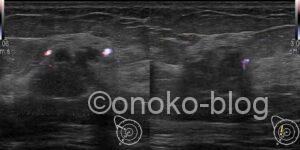

カラードプラでは辺縁に血流を認めます。

(だいぶゲイン上げてます)

カラードプラはあまり変わらないですね